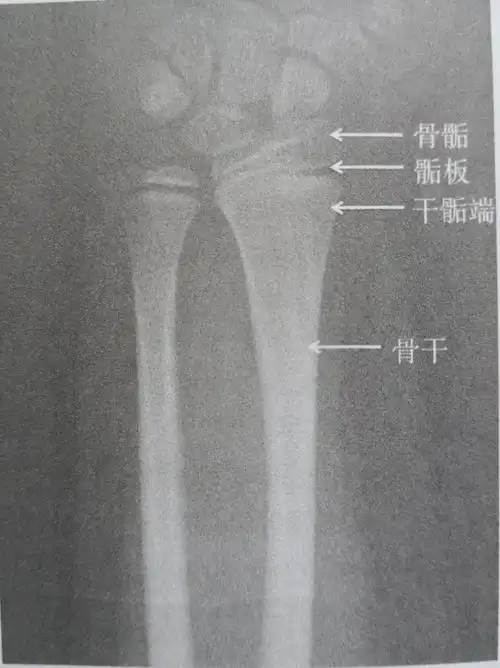

长骨两端膨大部分称为骨骺. 2.其骺端软骨层的细胞与骨的长度有关.

未成熟的长骨在解剖上分为:骨骺和骨干.

二,什么是骨骺线闭合 骨骺线是指长骨干骺端与骨骺之间的一层裙骨

骨骺与骨干之间有一层软骨层,医学上称之为骺软骨 ( 骨骺线).

x 线中骨与骨之间的一道间隔就是骨骺线未闭合前的形态.